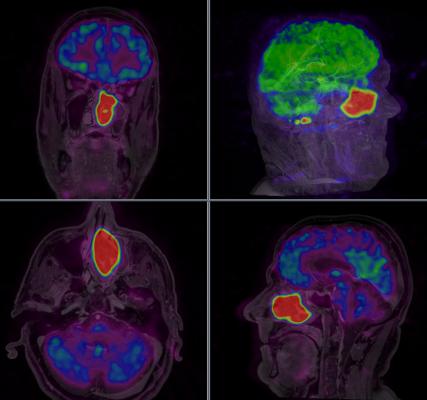

Every year Tc-99m is used in over 80 percent of all nuclear medicine imaging procedures in areas such as cardiology, oncology and neurology. Recently, Tc-99m produced with the QUANTM system was used to complete a Canadian multi-centre registration trial in bone imaging and thyroid function.